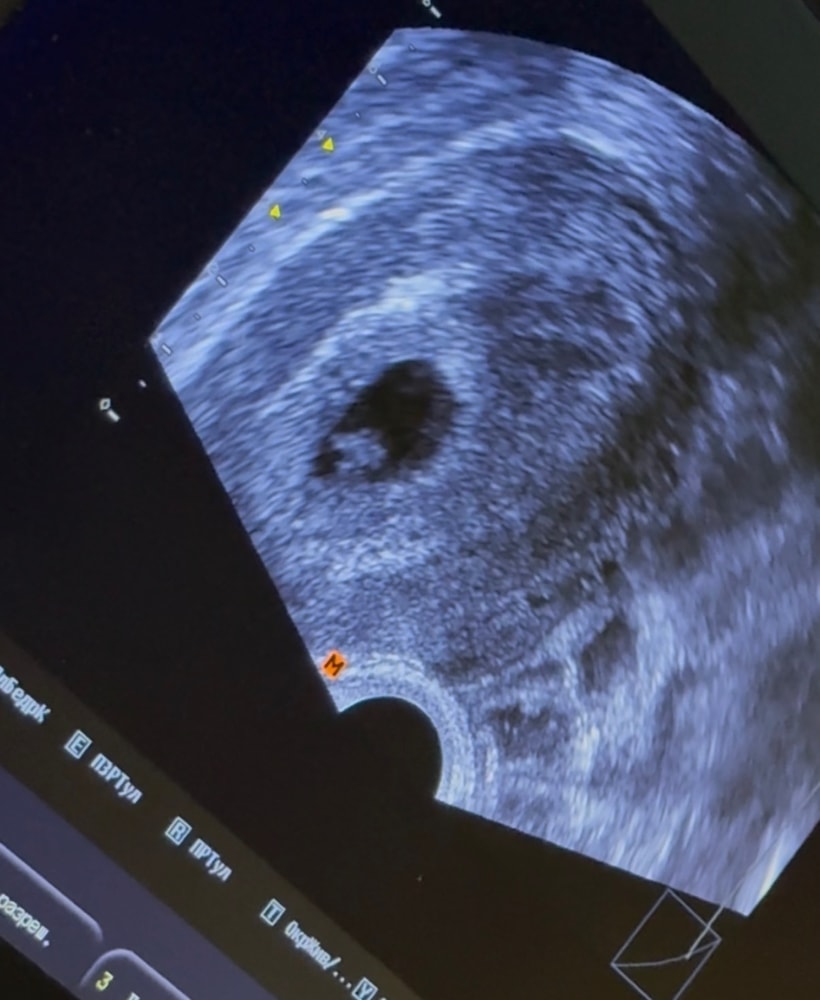

Узи на 31ДПП

Результаты УЗИСделали 27.09 второе узи, всё в порядке!

Сердечко бьётся❤️малыш растёт)